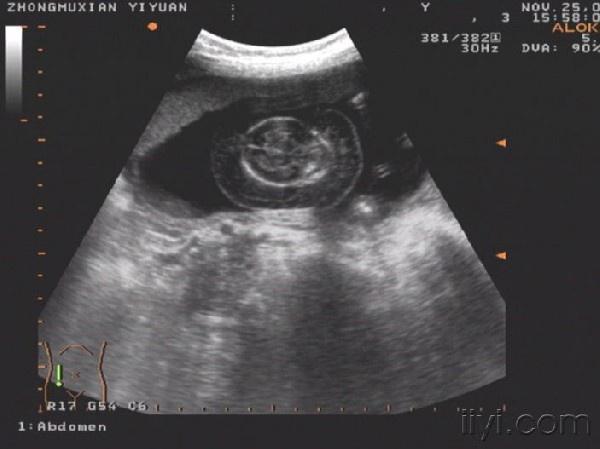

这个胎儿穿上了“太空衣”(典型胎儿水肿图片,值得分享!)

一位32岁经产妇,孕20周前来检查,发现胎儿被一层透明的膜状物包绕,从头颅到肢体,考虑胎儿水肿综合症!